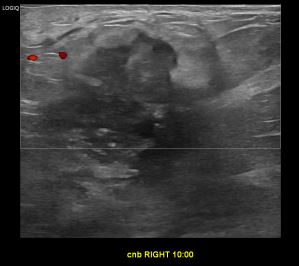

상기환자는 우측만져지는 멍울로 내원하신 50대초반

여성분으로 의심스러운 우측혹 조직검사 시행해 침윤성암 으로 진단되었습니다